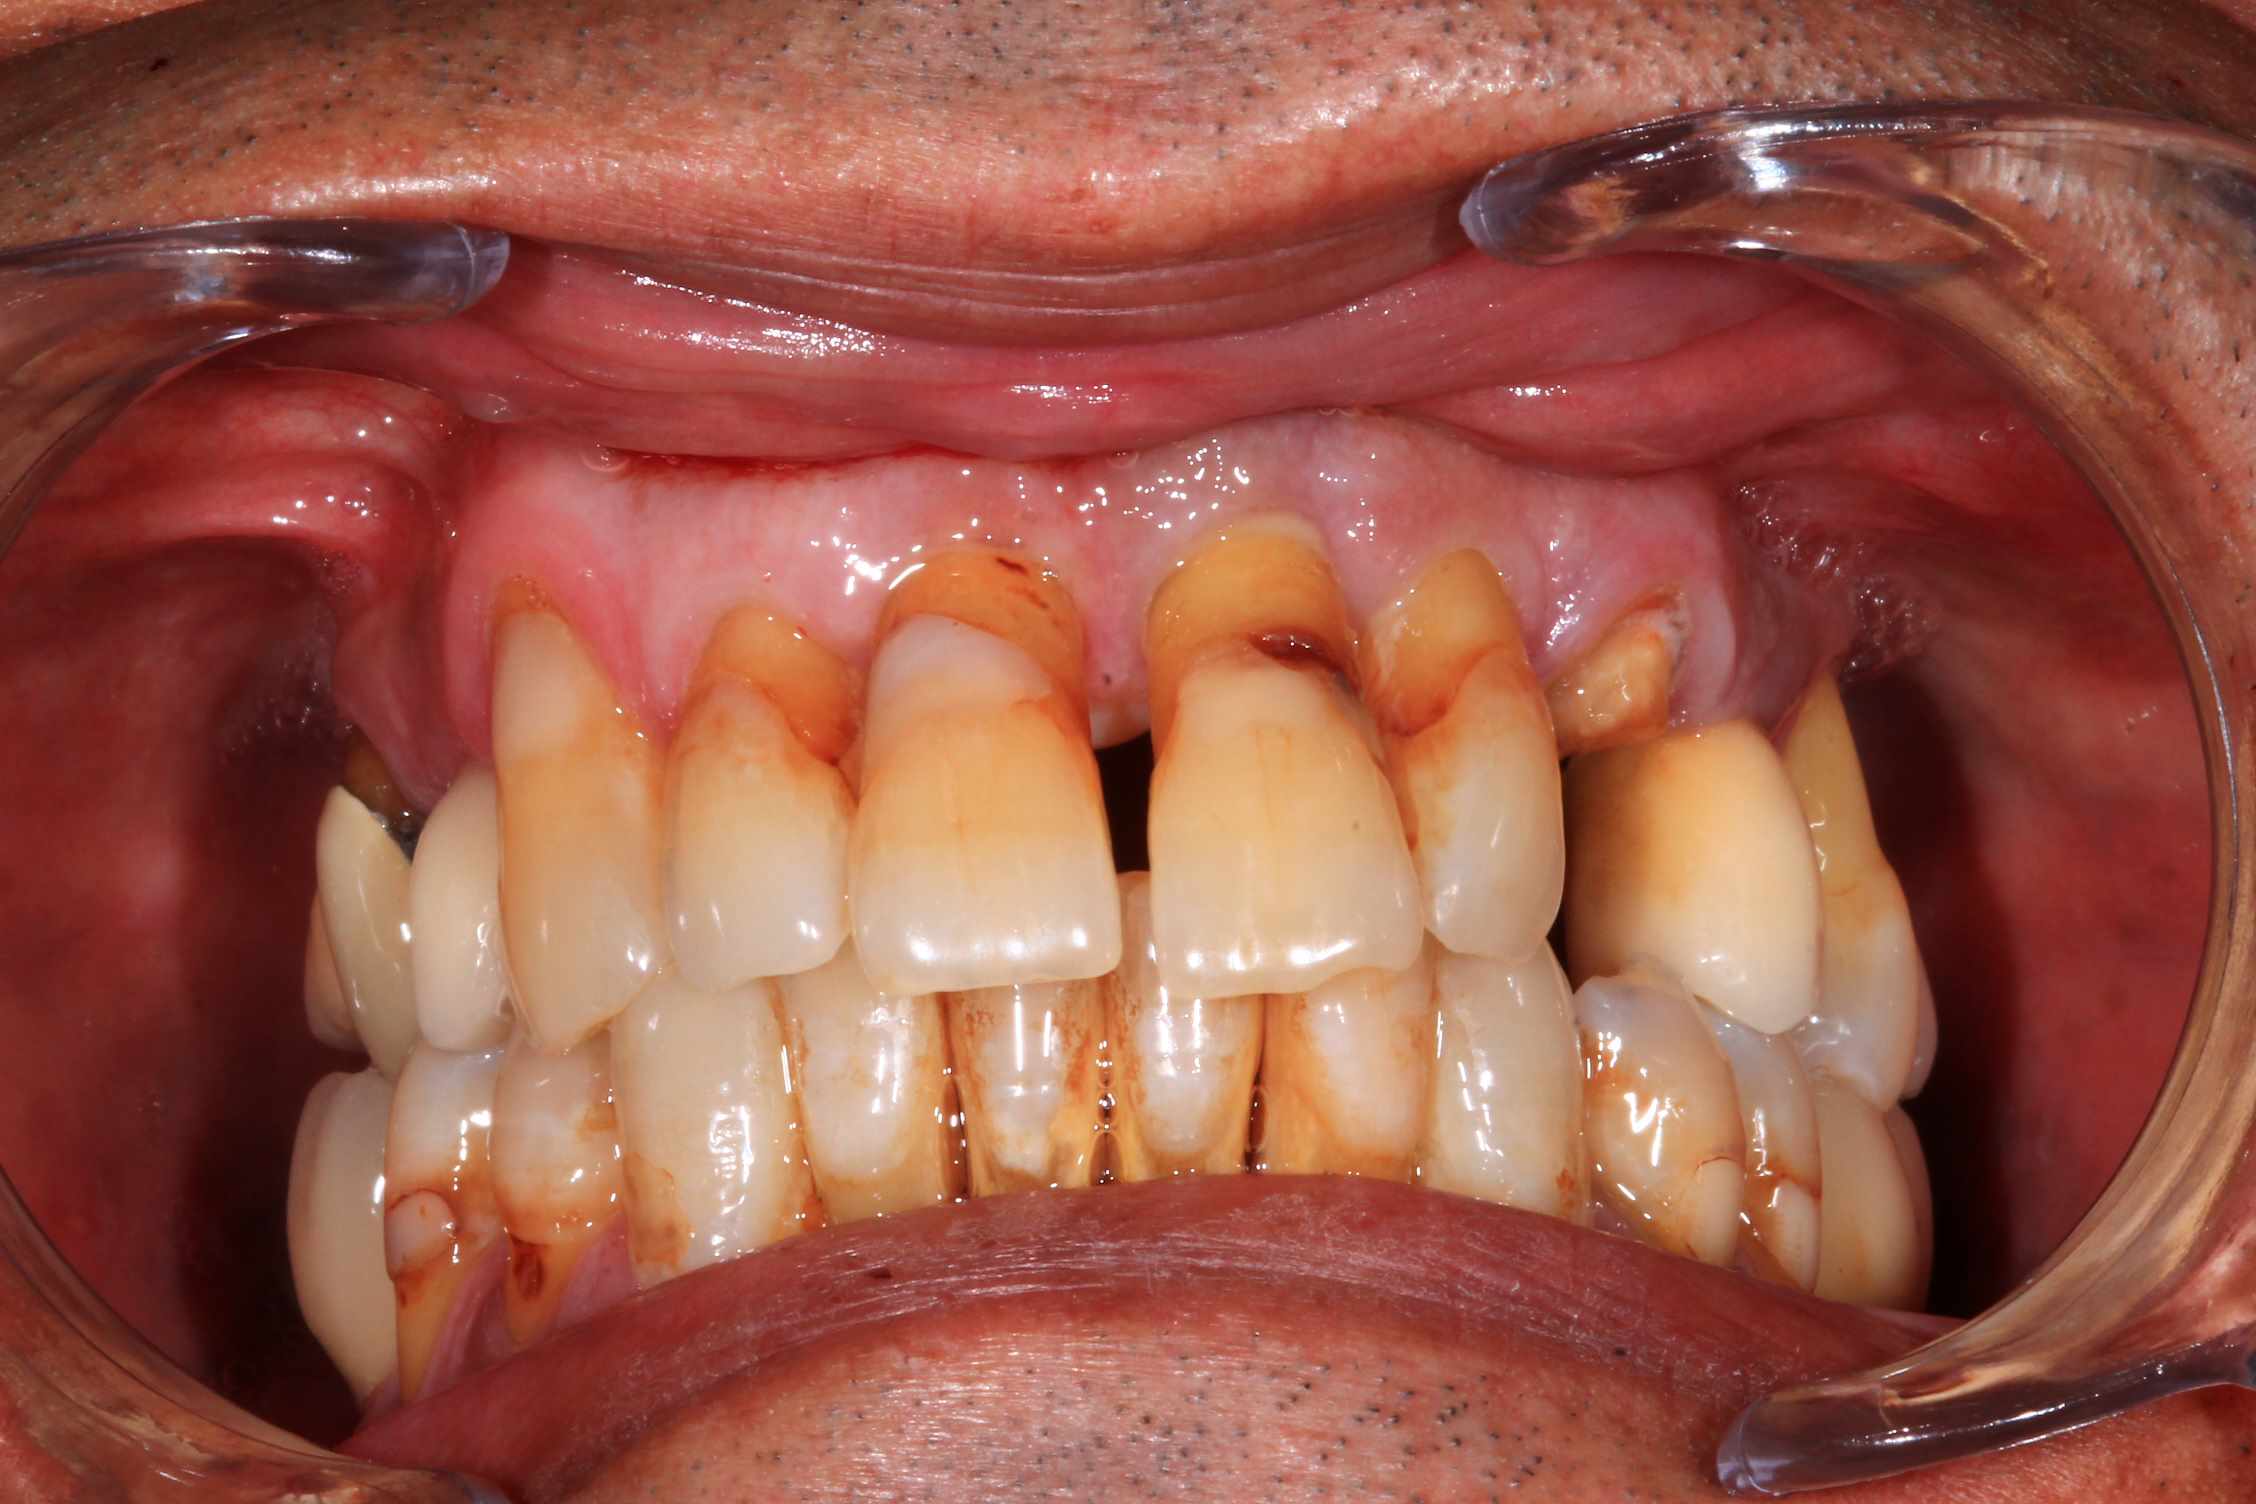

les 4 incisives sup sont à bout de souffle . Planification et export du guide résine avec blueskyplan. Export du modèle osseux et simulation de la chirurgie, comme d'hab selon mon protocole.

Quand les implants sont peu nombreux et proches, un guide résine est suffisant. C'est alors beaucoup plus rapide.

:) . effectivement terrain paro chronique, déjà traité il y a quelques année a paris. Plus ou moins stabilisé, pas de saignement, un peu de tartre en bas. des mobilités importantes sur les incisives antérieures qui, avec la facture de la 23 ont emporté ma décision. Solution alternative : stellite ? dans un an, tu extrais les dents support de crohet. Bridge ? cela me semble plutôt casse gueule.

Donc, implant , sur un terrain qui n'est pas idéal, certes, mais c'est souvent le cas.